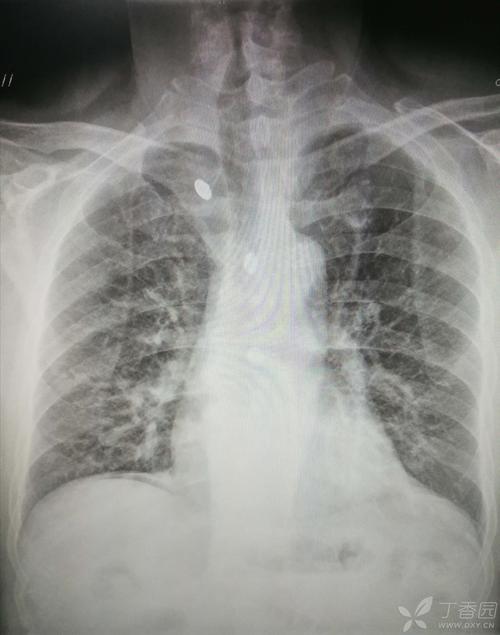

ct4228158f胸片示主动脉弓增宽主动脉瘤未排除纵

论坛各位便宜帮忙看我家人胸片是不是肿瘤?

看片诊病之典型急诊胸片分享

冯xx男51岁五官科诊咽炎,咳嗽行胸片常规检查,发现右下肺占位,ct同诊